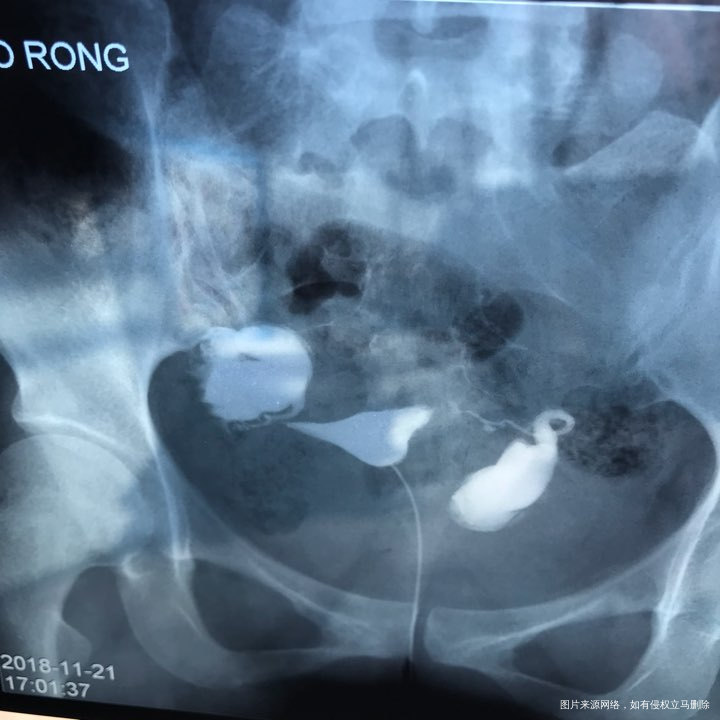

备孕时常1年,前期的检查都做了正常,帮忙看下我的输卵管造影片子吧??

您好,看着像是伞端堵塞了。

您好,考虑输卵管堵塞。建议遵医嘱。

您好,输卵管堵塞,建议切除输卵管做试管,保守保守治疗没有多大意义,觉着我的回复对您有帮助记着帮忙点击采纳,谢谢!